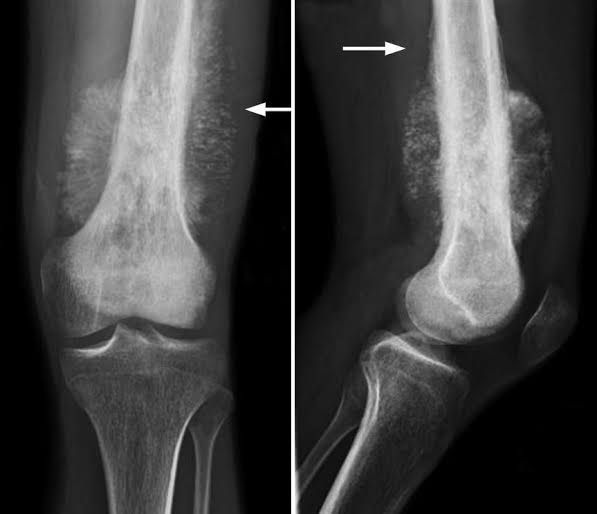

Osteosarcoma is a type of bone cancer that begins in the cells that form bones. Osteosarcoma is most often found in the long bones — more often the legs, but sometimes the arms — but it can start in any bone. In very rare instances, it occurs in soft tissue outside the bone.